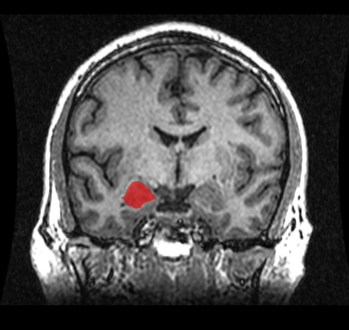

The diagnosis of temporal lobe epilepsy can include the following methods: Magnetic resonance imaging (MRI), CT scans, positron emission tomography (PET), EEG, and magnetoencephalography.[58]

Imaging[edit | edit source]

CT scan is useful as the emergency situations when the suspected cause of epilepsy is due to conditions such as intracerebral haemorrhage, or brain abscesses, or when MRI imaging is not readily available or there is any contraindications to MRI such as the presence of cardiac pacemakers or cochlear implants in the subject's body. CT scan also detect some abnormal calcifications in the brain that is characteristic of diseases such as tuberous sclerosis and Sturge–Weber syndrome. However, CT scan is not sensitive or specific enough when compared in MRI in detecting the common causes of epilepsy such as small tumours, vascular malformations, abnormalities of cerebral cortex development, or abnormalities in the medial part of the temporal lobe.[59]

MRI is the imaging choice when assessing those with epilepsy. In newly diagnosed epilepsy, MRI can detect brain lesion in up to 12 to 14% of the cases. However, for those with chronic epilepsy, MRI can detect brain lesion in 80% of the cases. However, in cases where there is definite clinical and EEG diagnosis of idiopathic generalized epilepsy, or Rolandic epilepsy, MRI scan is not needed.[59]